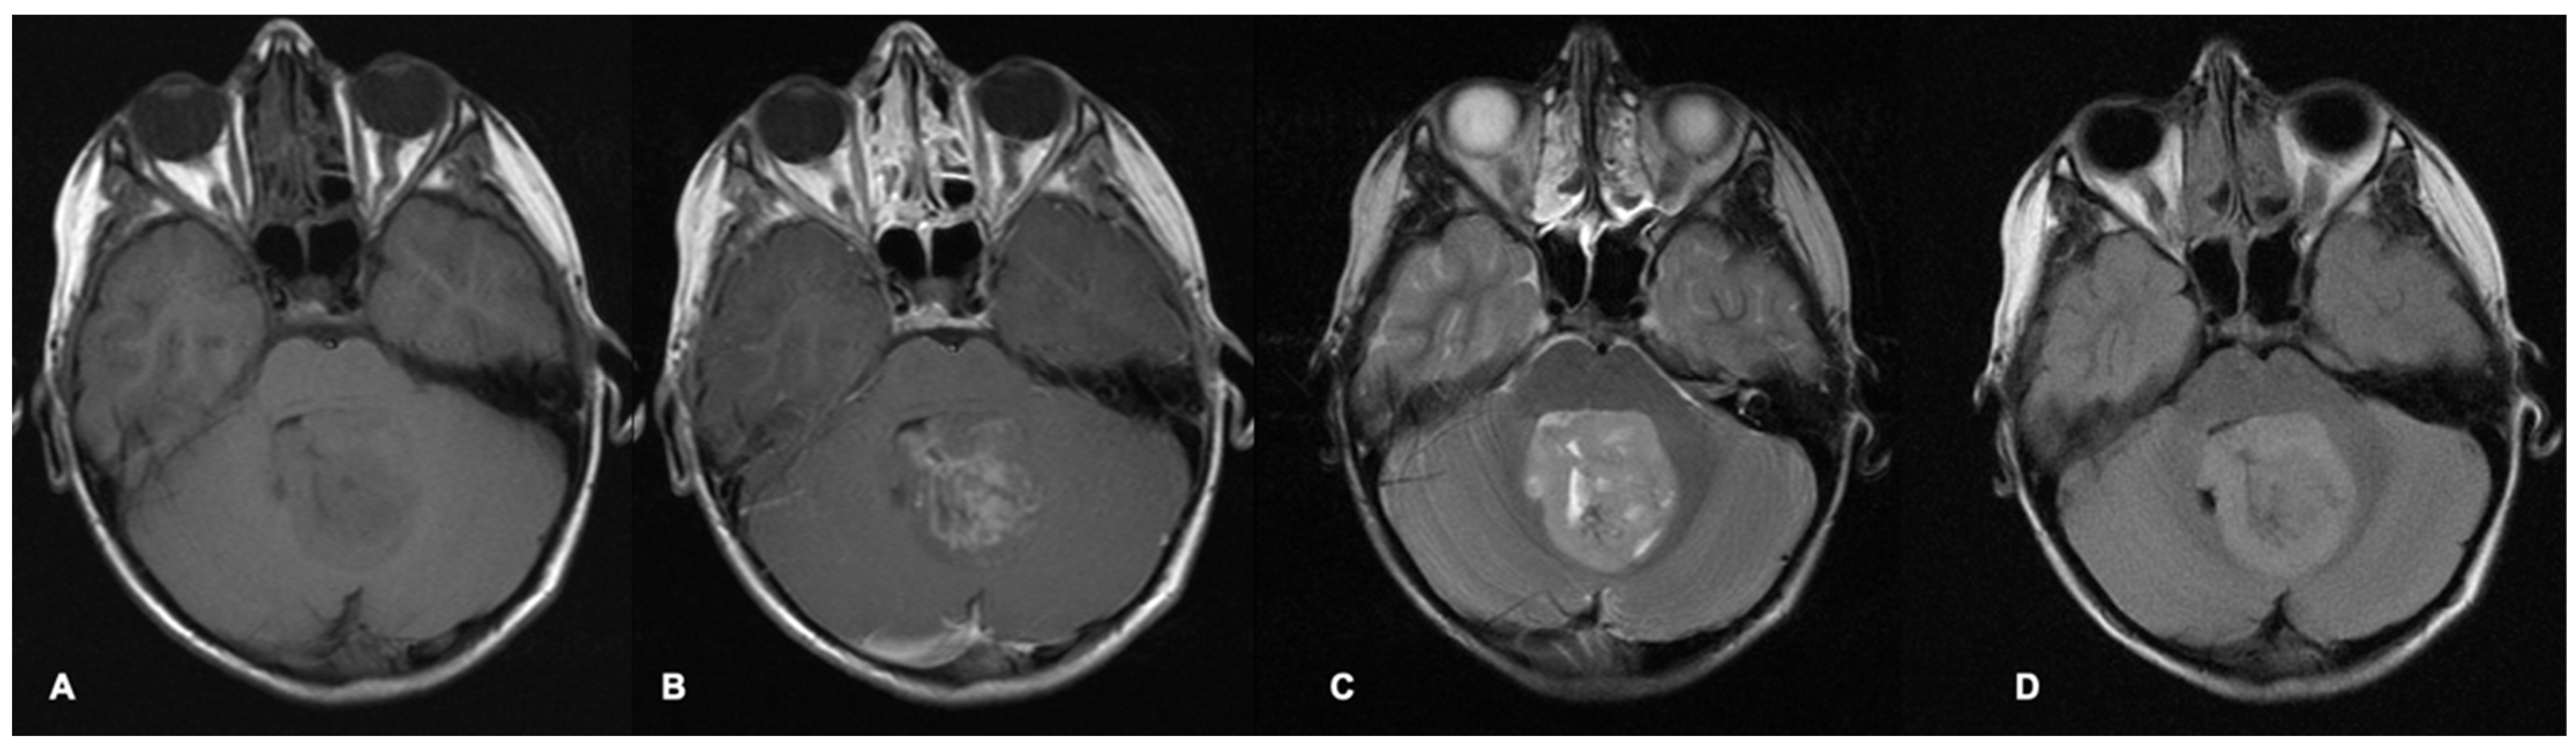

- Nowak, J.; Nemes, K.; Hohm, A.; Vandergrift, L.A.; Hasselblatt, M.; Johann, P.D.; Kool, M.; Frühwald, M.C.; Warmuth-Metz, M. Magnetic resonance imaging surrogates of molecular subgroups in atypical teratoid/rhabdoid tumor. Neuro-Oncology 2018, 20, 1672–1679. [Google Scholar] [CrossRef]